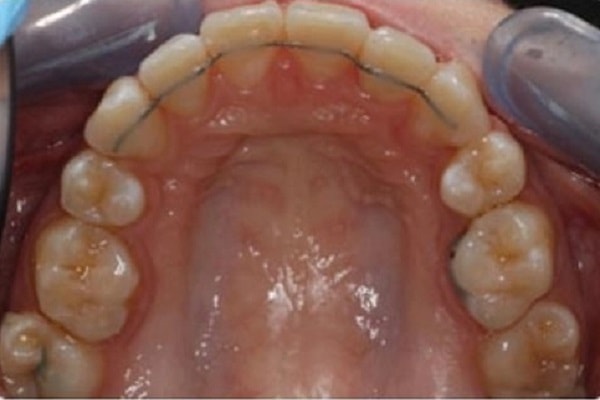

Lingual braces are just like traditional braces, only they are worn on the inner surfaces of the teeth. It is a more discreet and effective method for those who do not want their braces to be noticed. They are especially preferred by people who participate in contact sports and play wind instruments.

Self-ligating braces are similar to traditional metal braces. Instead of elastic ligatures, they have a self-ligating mechanism that holds the archwire in place. Lingual braces in Turkey can reduce friction and are used for a potentially shorter treatment time.